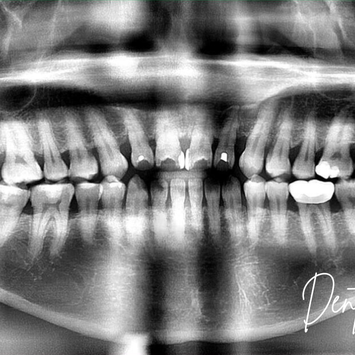

Surgical Removal of Impacted Upper Left Wisdom Tooth (#18) and Extraction of Tooth #17

Tooth #18: Partially buried in bone; impacted.

Tooth #17: Periodontal-endodontic involvement.

Pre-operative CBCT taken; no additional pathology noted.

CBCT reviewed.

No proximity concerns with IDN or maxillary sinus.

Post-operative Imaging:

Post-op CBCT confirmed no root remnants.

IDN and maxillary sinus intact and not involved.